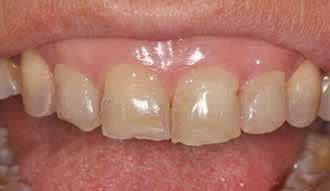

Hölgy páciensem az első konzultáció során tipikus kórtörténetet vázolt fel: Gyermekkora óta szeretett volna fogszabályozó készüléket, hiszen mindig is zavarta a class 2-es eltérésnél tipikusan jellemző nagy overjet (1-3. képek), és természetesen az ezáltal kifelé álló felső metszőfogai, részben a felső metszők protrúziója, részben pedig a disztálisan elhelyezkedő mandibula miatt. Annak ellenére, hogy több fogszabályozó szakorvosnál is járt az évek során, de mivel saggitális eltérése és az alsó metszőfogak torlódása miatt négy kisőrlőfog extrakcióját, illetve emellett sokszor állcsont műtétet is javasoltak neki, nem vágott bele a kezelésbe (4-5. képek).

A fogorvosa – nagyon helyesen – felhívta a figyelmét, hogy parodontális státusza is valószínűsíthetően romlani fog az eltérése miatt, újabb kört futott, immár 39 évesen, de még mindig premoláris fogak húzása és állcsontműtét nélkül szerette volna a fogszabályozást.

A konzultáció során arról is beszéltünk – ahogy az ilyenkor lenni szokott –, sohasem szeretett igazán mosolyogni, de a Pitts Protokolloknak köszönhetően az arc- és mosolyesztétikai céloknak megfelelően kerül megvalósításra az okklúziós korrekció. Az okklúziós kezelési célok az alábbiak voltak: a felső és alsó fogív nivellálása és tágítása, az alsó fogsor/ mandibula mezializálása, valamint a harapás megemelése által a mélyharapás rendezése.